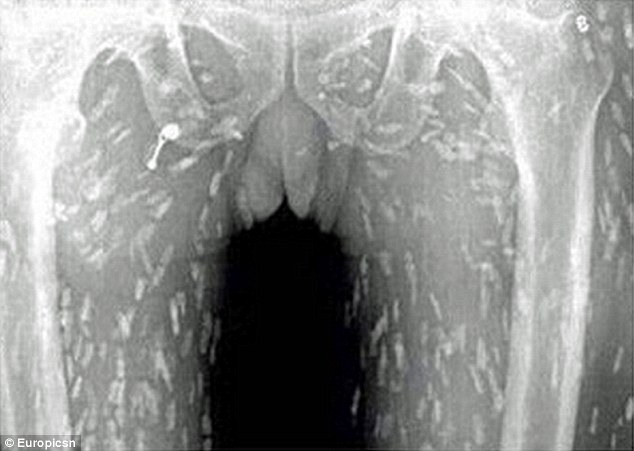

Չիանցու մարմինն ամբողջութկամբ որդերով էր պատվել: Դրանք ամենուրեք էին՝ ստամոքսում, մաշկի տակ և այլն: Նրան տեղափոխել են Չինաստանի Գուանդոնգ հիվանդանոց:Հետազոտությունները ցույց են տվել, որ հում ձուկն ուտելով մարդիկ կարող են փչացնել իրենց առողջությունը: Կարող են առաջանալ տարբեր վարակներ: